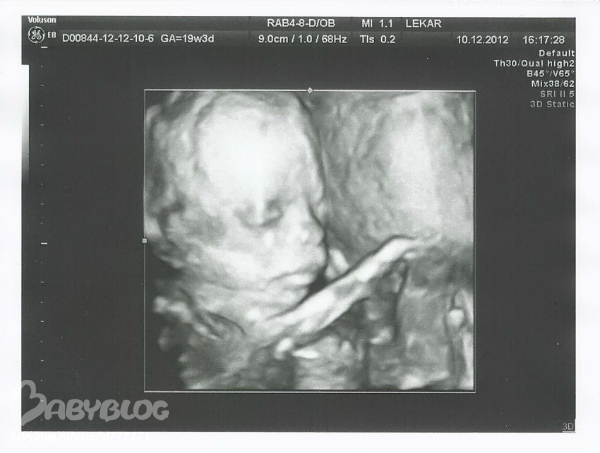

Екатерина в Клуб беременных 13 лет узи фото на 19 неделях ( наш Даник ))))) Посмотрите еще 20 записей на эту тему Отменить Ответить Марьяна ути карапузик какой:)))) 22.12.2012 Ответить Ариночка я не думала, что настолько все видно))) и как вы сами с мужем видите - похож ребенок на кого-то из вас или еще не понятно? 22.12.2012 Ответить Ариночка оооо!!!!!!! до чего техника дошла)))) скоро и я пойду на 3д, и 4д...)))))))) 22.12.2012 Ответить Лилия обалдеть!!как оказывается все четко видно)))красотулечка прям))) 22.12.2012 Ответить Галина 22.12.2012 Ответить Светлана здорово что у вас есть такое фото, нам так и не удалось посмотреть на свою ляльку в животике, хороший малыш растите здоровенькими)))))))))))) 22.12.2012 Ответить Екатерина всем спасибо 23.12.2012 Ответить Полноценный Новый год))) Гемотест или Инвитро Чаты Беременных Выберите чат: Январята-2026 Февралята-2026 Мартята-2026 Апрелята-2026 Майчата-2026 Июнята-2026 Июлята-2026 Августята-2026